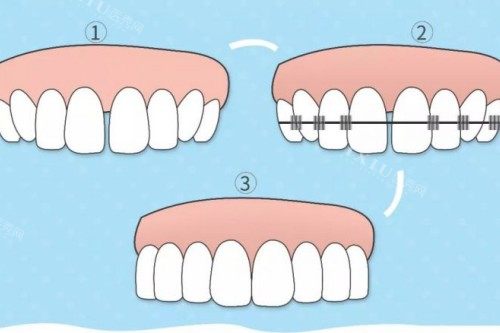

很多人认为牙齿矫正有严格的年龄限制,过了青春期就不能矫正了。然而,事实并非如此。牙齿矫正是通过正畸弓丝将排列不整齐的牙齿尽量排列整齐,让面型更加美观。虽然青春期是牙齿矫正的黄金时期,但只要 30 岁的成人身体健康、牙周健康,就完全可以进行牙齿矫正。现在有不少 40 - 50 岁的人也为了追求美进行牙齿正畸。只要患者牙周没有太大问题,也没有糖尿病、牙周病等,正畸的风险并不是特别大。

与青少年相比,30 岁矫正牙齿确实存在一些差异。青少年时期牙齿畸形明显,骨骼尚未发育完全,矫正速度相对较快,矫正后的结果也比较稳定。30 岁时牙齿骨骼发育已经完整,矫正时所需要的改善时间相对要长一些,矫正难度也会有所增加。不过,现代可靠的矫正技术和方法,能够在一定程度上弥补这些劣势,依然可以实现理想的矫正结果。

传统金属牙套

这是比较常见的矫正方式,矫正力度强,适用范围广。它的价格相对较为亲民,一般在 8000 - 15000 元左右。不过,外观上可能不太美观,而且佩戴时可能会有一些异物感。